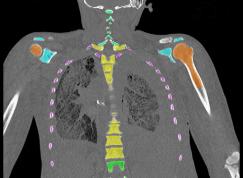

Dr. Wes Bolch’s Advanced Laboratory for RAdiation Dosimetry Studies (ALRADS) at the University of Florida is developing a suite of skeletal dosimetric phantoms for nuclear medicine patients aged from infancy to young adulthood. These are based on computer tomographic scan (CT-Scan) images taken post mortem. The ALRADS researchers have developed mathematical methods and software codes to render a series of two-dimensional CT-Scan image files into a three-dimensional voxel model of the whole body, including the trabecular and cortical bone structure of all parts of the skeleton. Among other activities, Dr. Bolch is contributing these ‘virtual phantom’ models to the ongoing work of the International Commission on Radiological Protection’s (ICRP’s) Task Group on Internal Dosimetry (INDOS). The three-dimensional modeling techniques developed by ALRADS are directly applicable to USTUR’s case studies – of elderly donors.

The Registries are therefore especially fortunate to host one of ALRADS’ graduate students, Deanna Hasenauer, for a 3-month DOE-sponsored practicum study with the aim of initiating ‘virtual phantom’ modeling of selected USTUR whole body cases.

CT-Scanning – Kadlec Medical Center, Richland, WA

The Director and technical staff of Kadlec Medical Center’s Diagnostic Imaging Unit have volunteered to carry out the CT-scan imaging for this DOE Practicum research project. The photo shows Deanna (center) with Traci McCoy (left) and Melissa Sloan, Kadlec CT-scan specialists, preparing to run the Case #0102 skull phantom through a GE Lightspeed 16 (16 slices per rotation) scanner. See some of the initial images below – and watch this space for further developments!

These CT slices are of the Case 0102 phantom cranium. Views were selected form the transverse, coronal, and sagital planes.